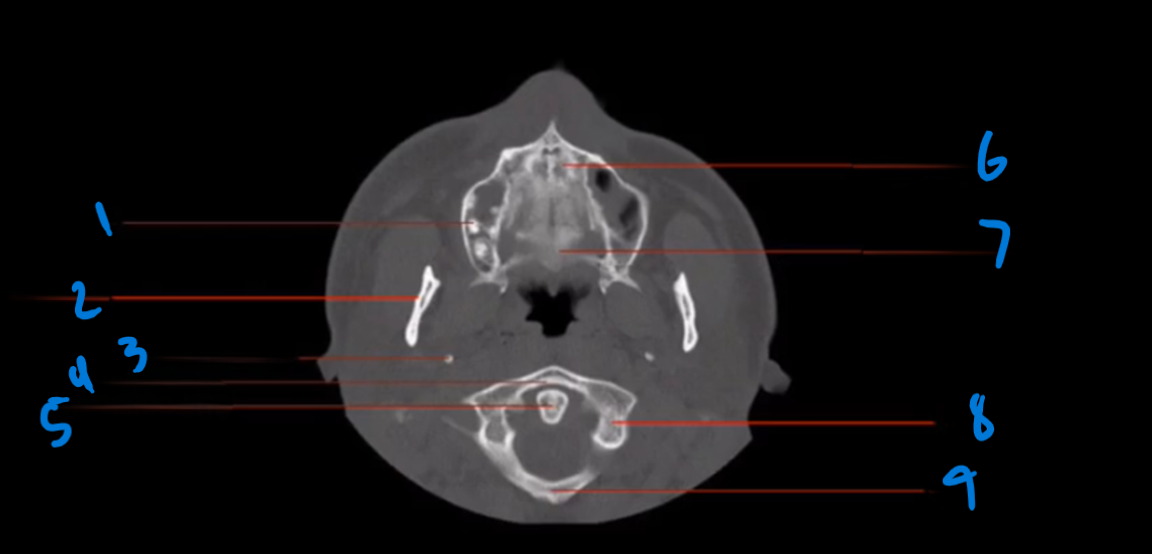

Landmark 1?

Maxillary Bone

Landmark # 2

Maxillary sinus

Landmark #3?

Coronoid process, mandible

Landmark # 4 called?

Mandibular condyle

Landmark # 5?

Carotid Canal

Landmark # 6?

Jugular Foramen

Landmark # 7?

Nasal Septum

Landmark # 8

Nasolacrimal duct

Landmark # 9

Zygoma

Landmark # 10

Zygomatic arch

Landmark # 11?

Clivus

Landmark # 12

External Auditory Meatus

Landmark # 13

Mastoid Air Cells, Temporal Bone